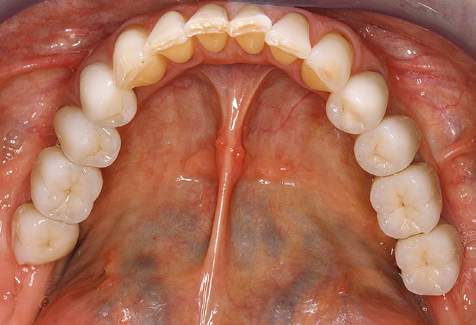

Standardised and regular risk-adapted care in the scope of SPT is the key to treatment success for the clinical long-term success in periodontically compromised patients. This is particularly true for patients fitted with implants following successfully completed periodontal treatment (Fig. 11a and b).